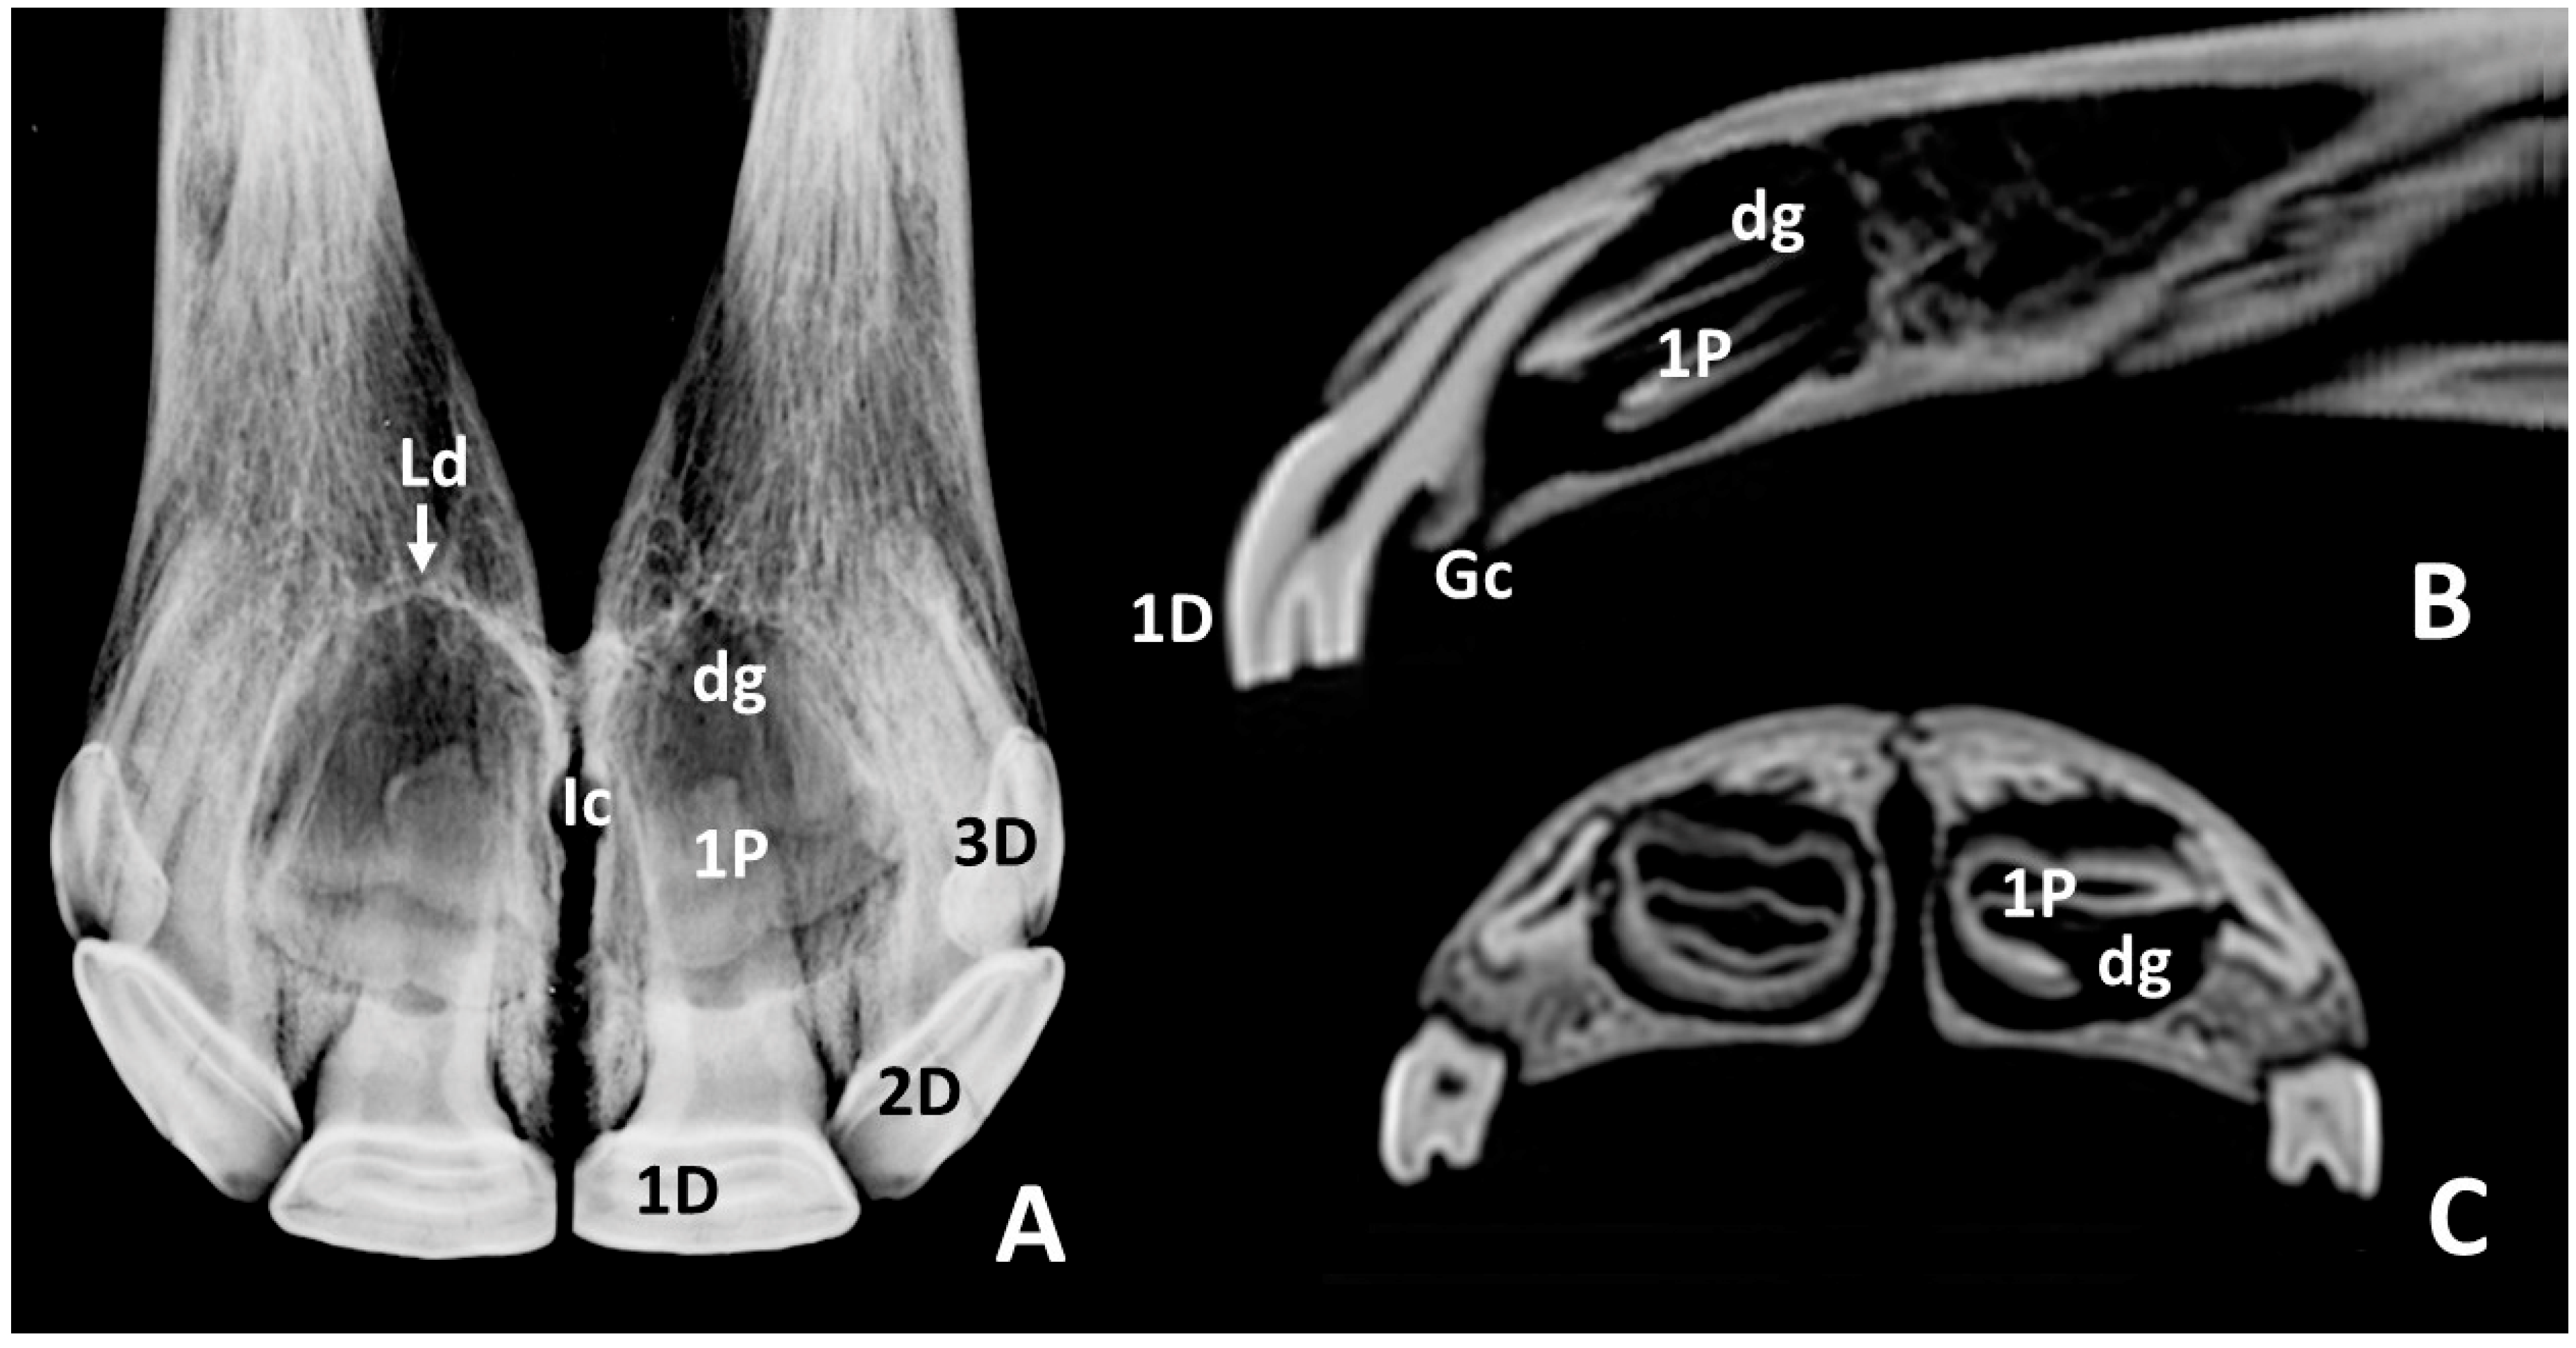

3.2. Radiographic and CT Studies

4.1. Deciduous Incisors: Radiographic and CT Studies

4.2. Permanent Incisors and Alveoli: Radiographic and CT Studies